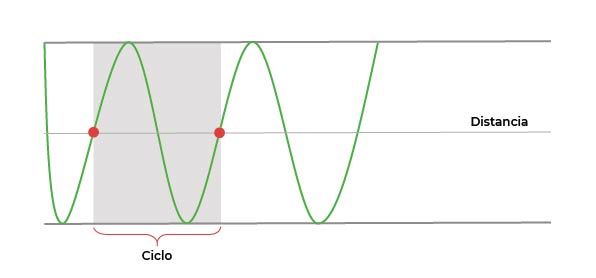

Ciclo

Cada vez que la onda atraviesa 2 puntos iguales en su trazado, forma un ciclo: